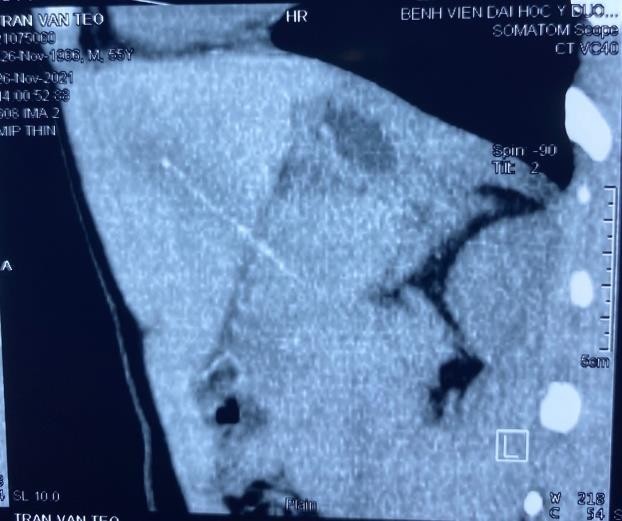

Bệnh nhân Trần Văn T. , 55 tuổi, địa chỉ tại Thủy Xuân, thành phố Huế nhập viện tại Trung tâm cấp cứu đa khoa và đột quỵ, Bệnh viện Trường Đại Học Y Dược Huế vì tình trạng đau bụng vùng thượng vị chếch hạ sườn phải. Khai thác tiền sử cho thấy bệnh nhân có thói quen ngậm tăm sau khi ăn và thỉnh thoảng trong khi đi ngủ, tình trạng đau bụng đã kéo dài từ khoảng 5 ngày nay. Thăm khám lâm sàng cho thấy bệnh nhân tỉnh táo, nhiệt độ 37,8oC, đau bụng chủ yếu vùng thượng vị chếch hạ sườn phải, ấn vào cảm giác đau nhiều hơn. Xét nghiệm máu cho thấy bệnh nhân đang có hội chứng nhiễm trùng với bạch cầu tăng 12,58 x 109/l (N=63%) và CRP tăng 18,94 mg/l. Hình ảnh chụp cắt lớp vi tính bụng cho thấy hình ảnh một dị vật dài 65mm (khả năng tăm tre) đâm xuyên vào phần gan trái và thân tụy, thâm nhiễm viêm xung quanh tạo thành ổ tụ dịch kích thước 34x28mm.

Hình 1: Hình ảnh dị vật đâm xuyên vào gan trái và thân tụy trên phim chụp cắt lớp vi tính

Đối với các dị vật đường tiêu hóa như tăm tre, vai trò của chụp Xquang bụng thường hầu như ít có giá trị. Trong trường hợp này, vai trò của siêu âm hoặc chụp cắt lớp vi tính bụng rất có giá trị trong việc phát hiện tăm tre bằng hình ảnh dị vật tăng âm trên siêu âm hoặc dị vặt tăng tỷ trọng trên hình ảnh cắt lớp vi tính. Quan điểm của Haidong Chen cho rằng đối với những cơ sở y tế có trang bị máy chụp cắt lớp vi tính có thể dựng hình ảnh được thì có thể xác định mối liên quan giữa dị vật (tăm tre) và các mạch máu ở thùy gan trái dễ dàng, điều này rất quan trọng vì trong trường hợp bệnh nhân được chỉ định phẫu thuật sẽ giúp cho phẫu thuật viên có thể đưa ra chẩn đoán và tiên lượng trước mổ một cách tương đối chính xác, làm cho hiệu quả của cuộc phẫu thuật sẽ thành công hơn.